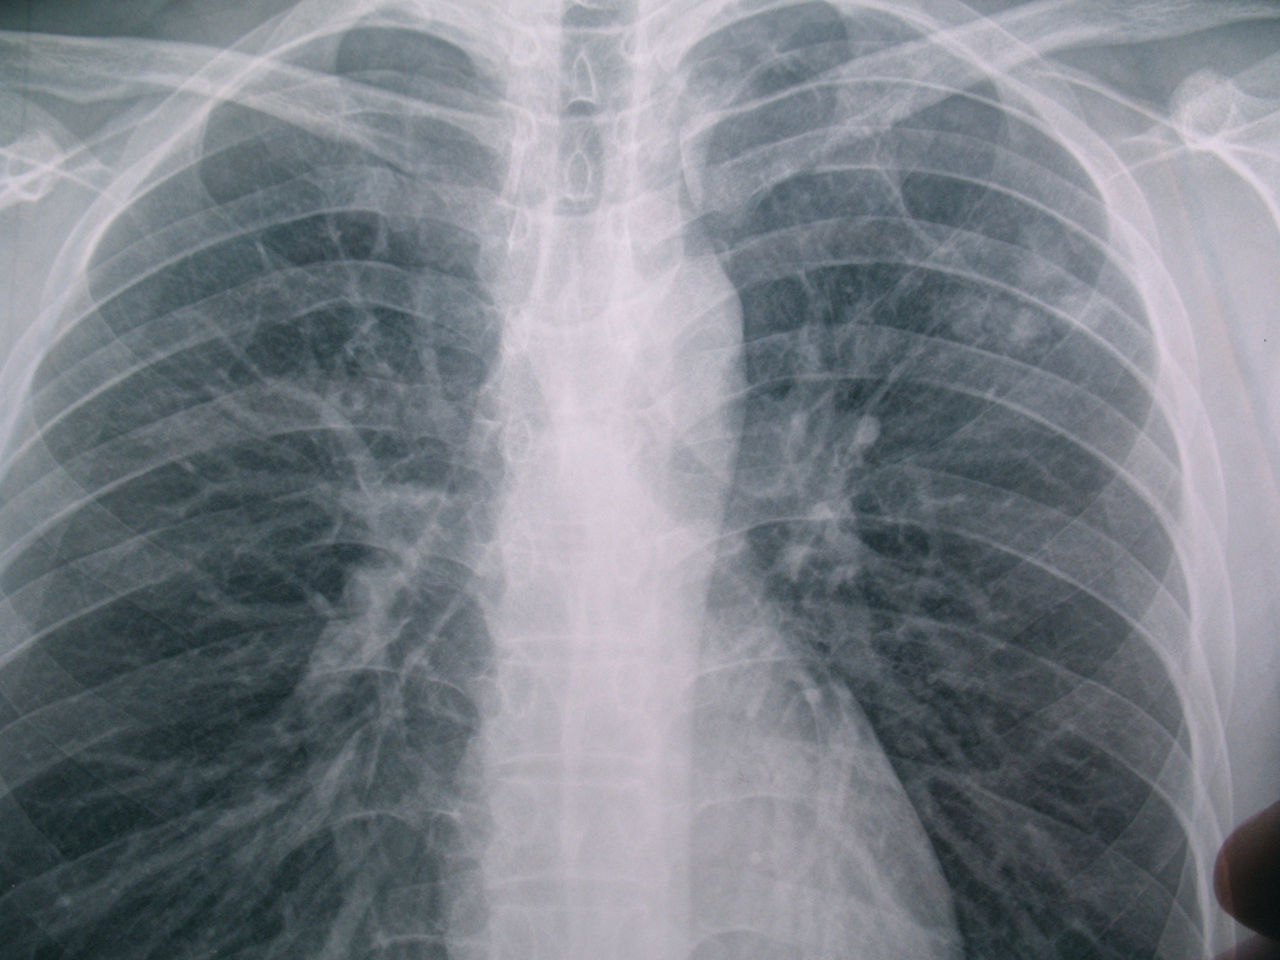

胸片正常图片 胸透

胸片正常图片 胸透,胸片正常图片胸透

胸部x光图像

那位专家能帮我看看这个胸片

胸片

影像解剖入门正常胸片怎么看